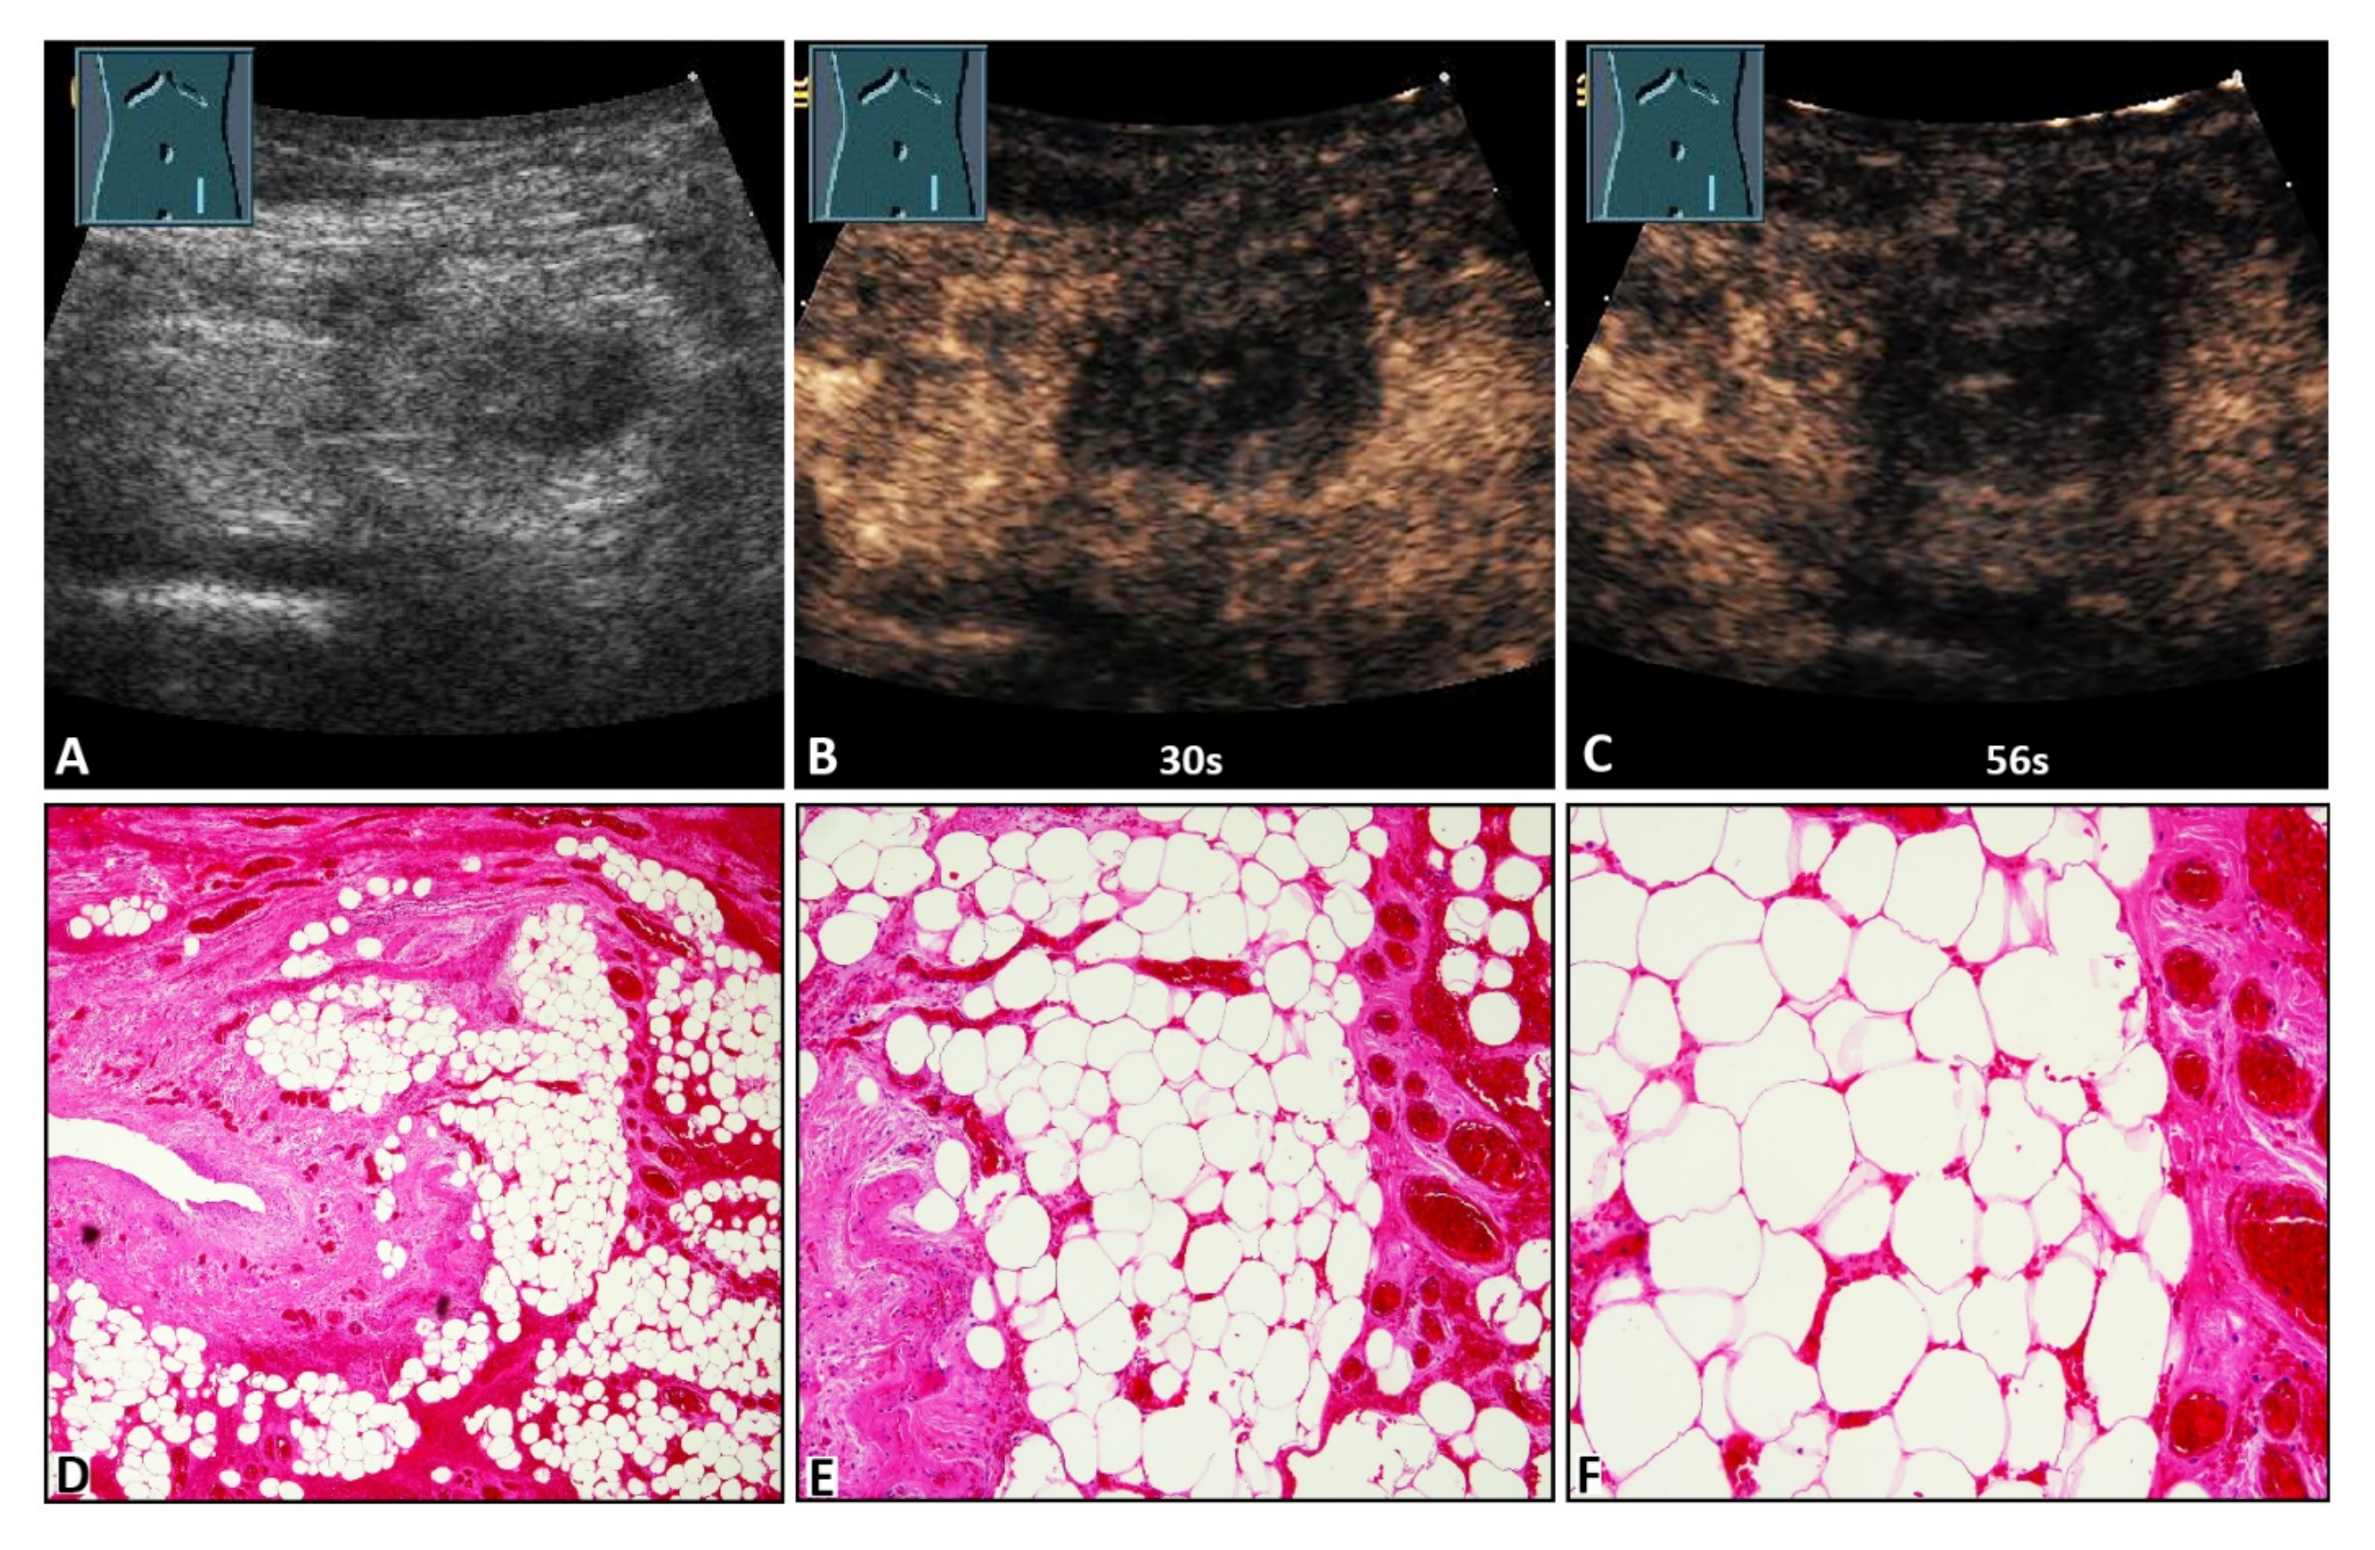

Figure 3.

A 47-year-old female patient with acute peritoneal pain in the left lower abdomen and a palpable inguinal-located tumor. (A) B-mode ultrasound shows a hyperechoic lesion with a central hypoechoic area. (B,C) On contrast-enhanced ultrasound, the lesion shows absent enhancement after 30 s and 56 s, and an omental hernia was diagnosed. (D) Omentum with partial fibrotic consolidation (on the left) and dilated hyperemic capillaries and hemorrhages (4× magnification). (E) Omentum with central necrotic fat tissue (missing nuclei), fibrosis (to the left), and dilated hyperemic capillaries and hemorrhages (on the right) (10× magnification). (F) Omentum with central necrotic fat tissue, and dilated hyperemic capillaries and hemorrhages (20× magnification).